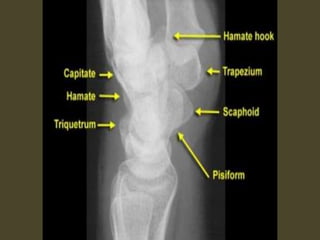

Wrist X-ray Anatomy.